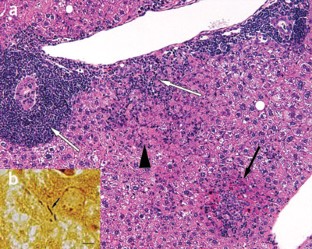

Fox, J.G. et al. Chronic proliferative hepatitis in A/JCr mice associated with persistent Helicobacter hepaticus infection: a model of Helicobacter-induced carcinogenesis. Infect. Immun. 64(5), 1548–1558 (1996).

Ward, J.M. et al. Chronic active hepatitis and associated liver tumors in mice caused by a persistent bacterial infection with a novel Helicobacter species. J. Natl. Cancer Inst. 86(16), 1222–1227 (1994).